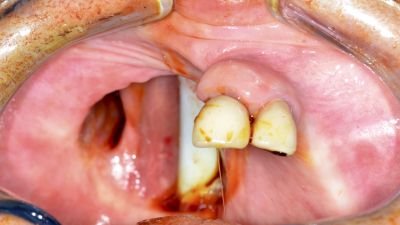

The Zygomatic Implant Perforated (ZIP) Flap technique involves the use of a zygomatic oncology implant perforated micro-vascular soft tissue flap for the primary management of maxillary malignancy.

• Immediate surgical reconstruction

• Microvascular free flap closure

• Zygomatic implant placement through flap

• Low-level maxillary malignancy (Brown Class II)

• Squamous cell carcinoma of hard palate

• Maxillary alveolar tumours

• Infrastructure maxillectomy defects